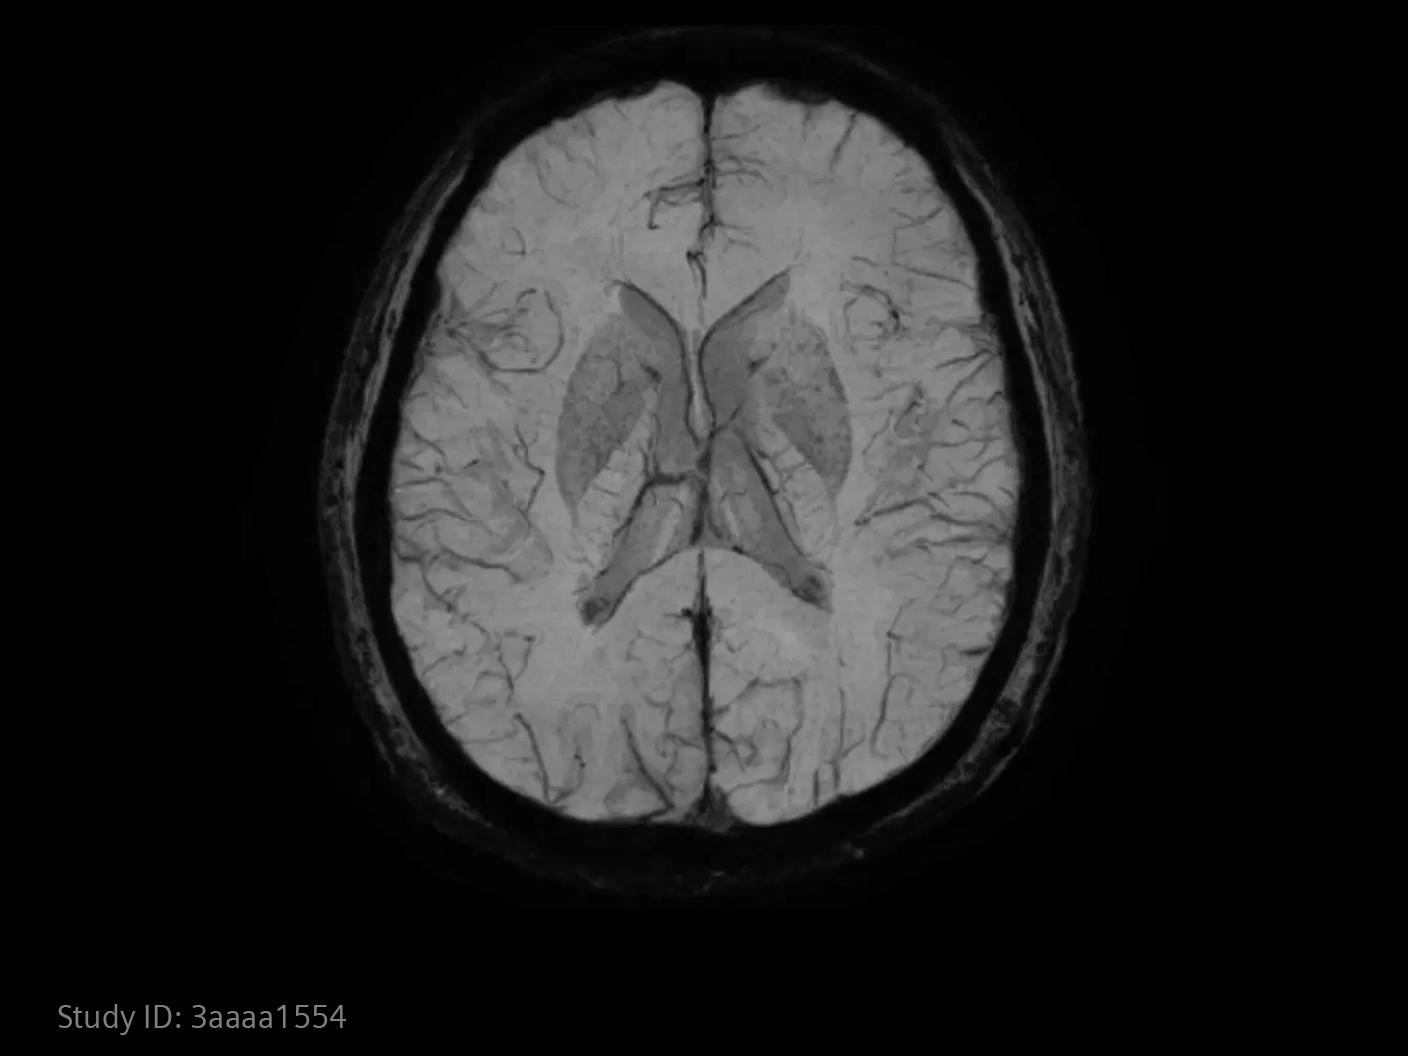

In stroke care, time is brain. Rapid and accurate imaging is crucial to assess the extent of brain injury and guide immediate treatment. Angiography, MRI, CT, ultrasound, and lab diagnostics are essential tools in identifying stroke type, location, and severity. Advances in imaging technology now allow for even faster acquisition, improved resolution, and enhanced visualization of brain tissue and blood vessels. Innovations such as perfusion imaging, real-time vascular mapping, and AI-assisted diagnostics are transforming stroke workflows and enabling precise, timely interventions.